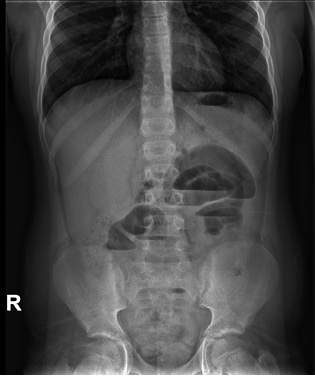

In children with bilious or fecaloid vomiting, distension and abdominal pain and those who have a history of having previously undergone surgical interventions, adhesions or fibrous flanges may have developed that generate obstructive symptoms that, as they evolve, can generate: ischemic areas, hypovolemia due to third space, shock and sepsis. The risk described in retrospective series is 1-5% in the 5 years following the operation, with a higher risk in patients who have undergone reoperation, who have suffered peritonitis or in whom the ileum has been affected(24). The key test, in addition to the high index of suspicion based on the history, is the abdominal x-ray, which will show distended loops, and if the patient can remain upright in a standing position, air-fluid levels (Fig. 2). In infants, another option is the horizontal ray. The initial treatment is to keep them nil-by-mouth, decompress with a nasogastric tube and administer intravenous fluids. If there is no improvement or there is evidence of intestinal ischemia, the treatment will be surgical.

Figure 2. Simple abdominal x-ray, performed in a standing position, in a child with intestinal obstruction. The characteristic air-fluid levels are visible.